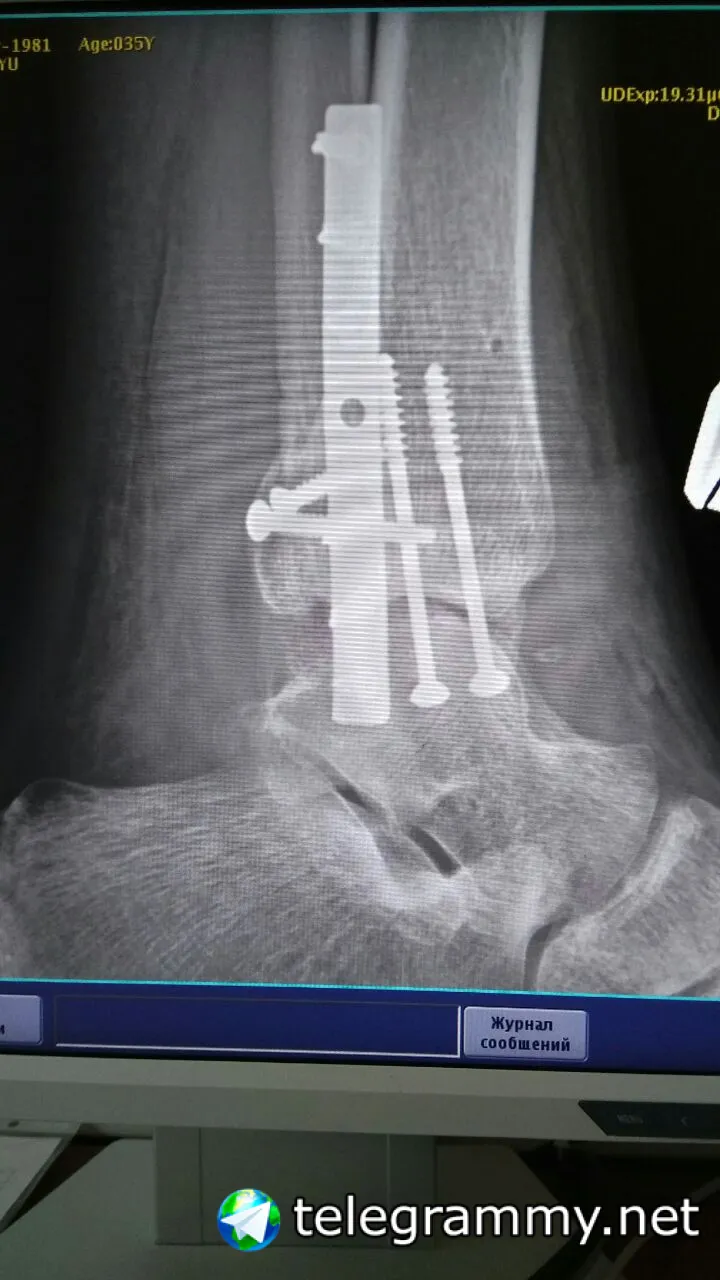

Когда травма была? Скинь рентген снимки до операции и после операцит

Скинь снимки и даты травмы,операции и выписки

Eugene

Травма 9.11.2016, операция 24.11.2016